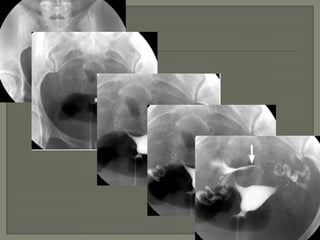

Se toman 4 proyecciones básicas:

La primera es obtenida durante la fase temprana de llenado y es

para evaluar cualquier defecto de llenado o anormalidad de los

contornos. En esta fase los pequeños defectos de llenado son mejor

vistos.

La segunda imagen es obtenida con el útero bien distendido, la

forma del útero es mejor evaluada en esta proyección, aunque

pequeños defectos de llenado se pueden perder.

La tercera imagen es obtenida para demostrar y evaluar las trompas

de falopio

La cuarta imagen debe de mostrar paso libre del medio de contraste

a la cavidad peritoneal.

Placas adicionales pueden ser obtenidas para documentar cualquier

anormalidad. Proyecciones oblicuas de las trompas pueden ser

obtenidas para desdoblar la imagen de la trompa o desplazar

estructuras superimpuestas.